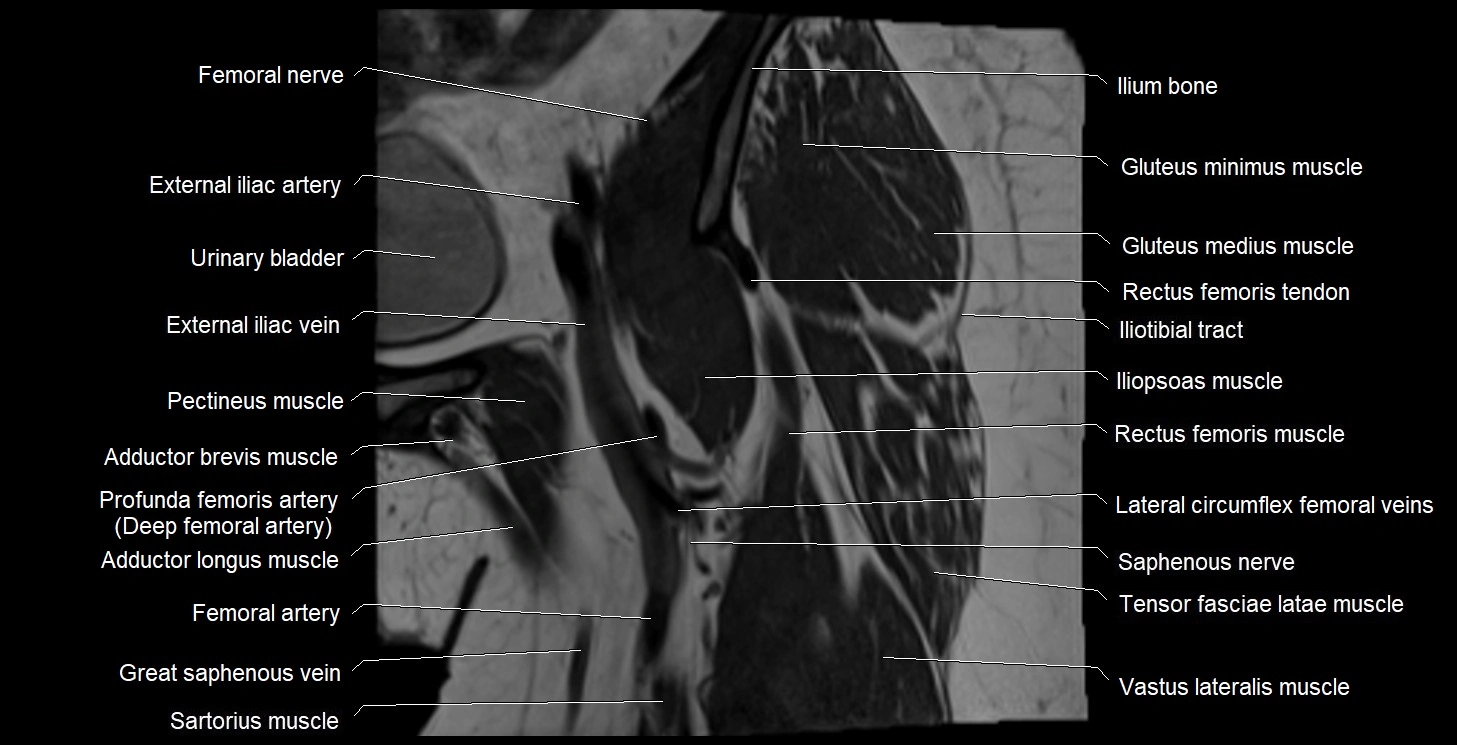

- External iliac artery

- External iliac vein

- Femoral nerve

- Femoral vein

- Gluteus medius muscle

- Gluteus minimus muscle

- Iliopsoas muscle

- Iliopsoas tendon

- Iliotibial tract

- Ilium bone

- Lateral circumflex femoral veins

- Pectineus muscle

- Rectus femoris muscle

- Rectus femoris tendon (Proximal tendon of rectus femoris)

- Saphenous nerve

- Sartorius muscle

- Superficial femoral artery

- Tensor fasciae latae muscle

- Urinary bladder

- Vastus lateralis muscle